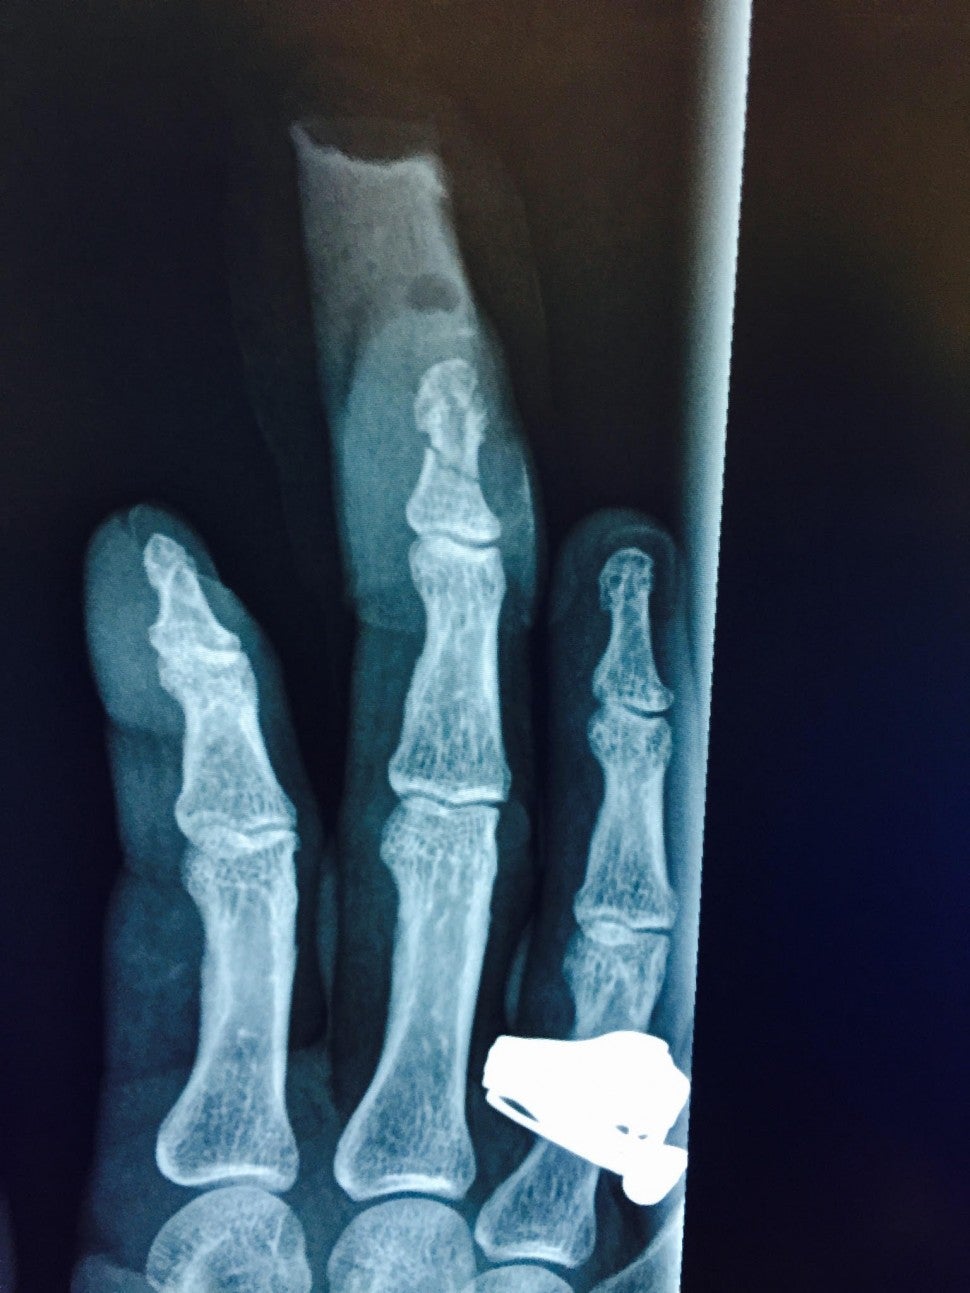

The documents continue, stating that Depp's "hand was resting on the marble top of the bar, the bottle smashed against his finger, severing the top of his finger and fracturing multiple bones in it. Ms. Heard then put a cigarette out on [Depp's] right cheek."

A photo obtained by ET shows Depp laying down on a hospital gurney with his hand bandaged a few hours after the alleged incident. Depp's legal team claims the cigarette burn on Depp's cheek is also very visible in the photo.